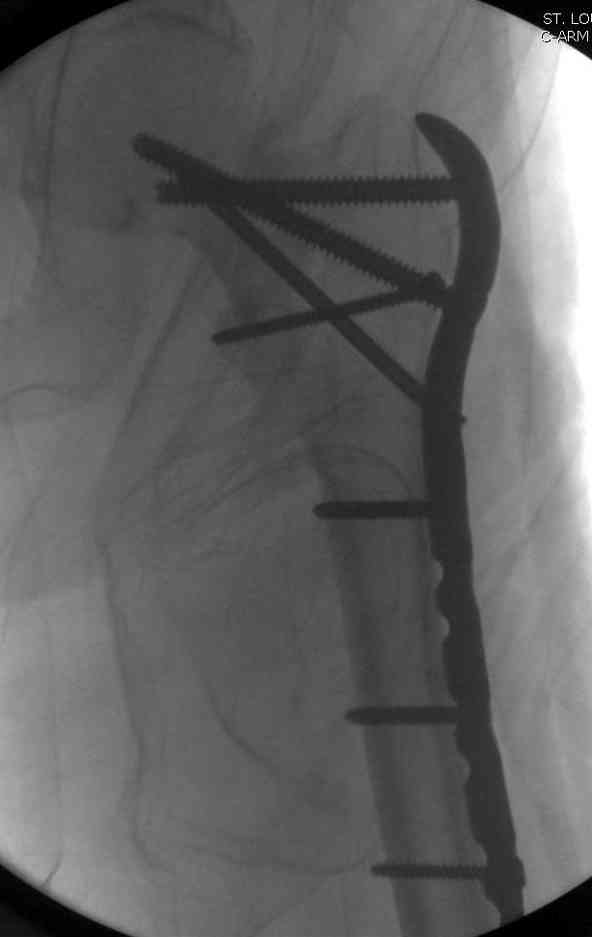

23.08.07г. на форуме был представлен больной 68 лет с диагнозом: несросшийся подвертельный косой перелом. http://www.weborto.net/forum/1187804790/ Больной после неудачной операции в одном районе в течении 7 месяцев был прикован к постели, с пролежнями в обл. крестца. Больной в течении 10 дней подготовлен к операции, НВ-153, эритр.-4,5, соэ-7, ВСК-3-3,40. ПТИ-81.ФНГ-3100. Мочевина, билирубин, АЛТ,АСТ в пределах нормы. Для остеосинтеза готовили пластину клинковую, штопор Сиваша . Во время операции дистальный отломок легко мобилизовали, проксимальный отломок был ротирован и сильно приведен медиально( m. iliopsoas), а также сильно замурован плотной как хрящ рубцовой тканью. Линия излома косая около 10 см., наружная стенка большого вертеля почти не было. У малого вертеля отсекли сухожилие m. iliopsoas и дальше на глубине начали распатором мобилизовать конец проксимального отломка, который был сильно приведен и находился глубоко , когда начали отделять изогнутом распатором заднюю часть конца и чуть подтянут отломка и тут начался сильнейшая кровотечения, фонтаном, найти сосуд и остановить кровотечение в ране не удалось, сосуд вместо с рубцовой тканью ушел назад и медиально отломка. Срочно рану туго тампонировали и остановили кровотечение, вызвали сосудистого хирурга,но их не нашли, оказалась один в отпуске, двое на экстренном вызове в районах. Передным доступом (по L. vasorum ) обнажали бедренную артерию, провели резиновую держальку и временно сосуд зажали, открыли рану , убрали тампон, но на глубине в толще рубцовых тканей поврежденный сосуд найти не удаётся. Поэтому переднюю рану расширили вниз, при ревизии бедренная артерия не повреждена, а глубокая бедренная артерия повреждена пристеночно, примерно на 2-3см от место отхождения от бедренной артерии, не доходя до ответвлений на огибаюших артерий. А одноимённая вена повреждена на протяжении около 3х см, и в данный момент восстановить не удается и пришлось перевязать оба конца, на артерию наложили поперечный сосудистый шов, бедренную артерию освободили, кровоток восстановился. Но теперь начала вся рана кровить! Венозный застой! К этому времени состояние больного резко ухудшилось, наступил клинический смерть, с трудом реанимировали, вроде б и кровотечение остановилось, как а/д подняли до 100/60мм опять начался кровотечение, коагулятором остановить не удаётся, рану туго тампонировали, перелито больше одного литра эр. массы и плазмы,и ешё кровозаменители, стабизол, рефортан и др. а/д держим 90/60, интесивная терапия против ДВС синдрома. Реаниматологи не разрешают производить остеосинтез, так как гемодинамика нестабильная , держиться под вазопрессорами. Через час состояние больного не улучшается , реаниматологи дали 10 минут и мы быстро кое как репонировали, остеосинтез продолной пластиной ЦИТО, но шурупы в проксимальном отломке плохо держутся, (остеопороз ), но другого выхода не было, для клинковой пластини просто небыло времени. Тканевое и капиллярное кровотечение продолжается, рану туго тампонировали и наводяшие швы на рану. Наложили гипсовой сапожок с деротатором. Больной находился в общей реанимационной отд. 20 дней и вышел из критического состояния. Но на контр. Р-грамме шурупы как и предпологали не держались, имеется ротация проксимального отломка, хотя ось бедра правильная и клинически деформации нет, даже определяется клиническая схватка . Я долго думал, вынести это на форум или нет, позвонил Челнокову А Н, он сказал <надо быть честным до конца, доложил на форуме, надо сообшить и о резултатах> Уважаемые коллеги! Какие были допушены ошибки? И какие рекомендации будут теперь? . P. S. за некачественный р-снимок прошу прошения!

Из-за ослабленного латерального кортекса в проксимальной части бедра (прорезавшийся первичный неудачный штифт) штифт для фиксации не годится. Потом для установки современных блокирующих штифтов необходимы дополнительные оборудования и опыт применения.

Адекватная фиксация достигается длинным 95 градусным Blade Plate, где клинок пластины, связывая головку со средней трети бедра, создал бы условия для сращения.

Другой вариант пластины, это Synthes Proximal Locking Plate предназначенный для лечения прксимальных переломов бедра, где три шурупа: два 7.3 мм, введенных в головку под углом 95, 120 и 5.0 мм в 130 градусов, создают угловую стабильность.

Профилактику прорезывания шурупов в кости можно добиться введением в отверстие цемента, потом проведением шурупа, цемент, застывая, удерживает шуруп в правильном положении.